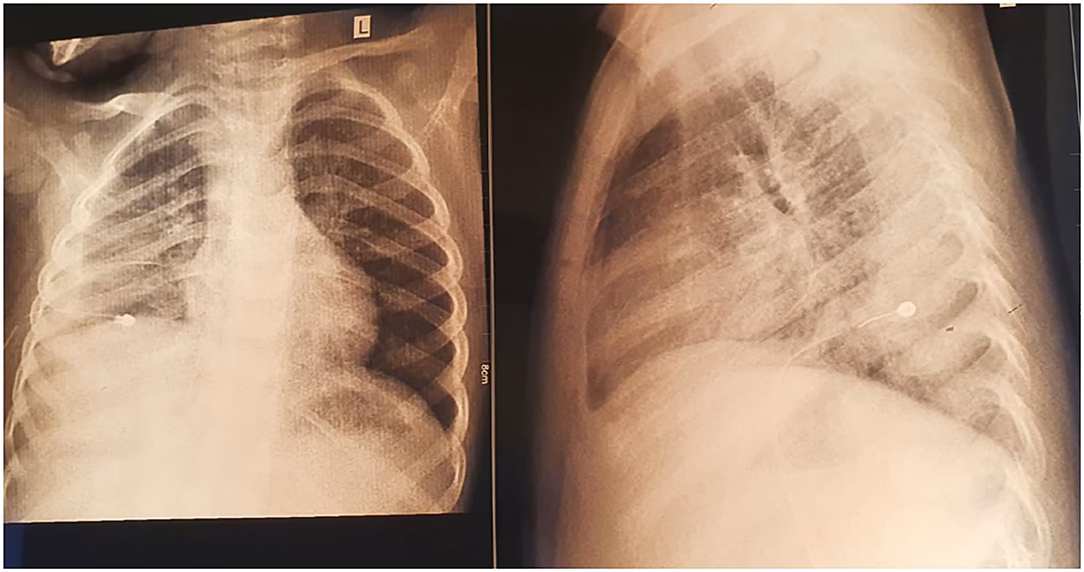

- Røntgenbilleder: Et røntgenbillede af lungerne kan bekræfte, at der er lungebetændelse, og vise tegn som inflammation eller væskeansamling (pleural effusion), men det kan ikke afsløre, hvilken mikroorganisme der er årsagen.